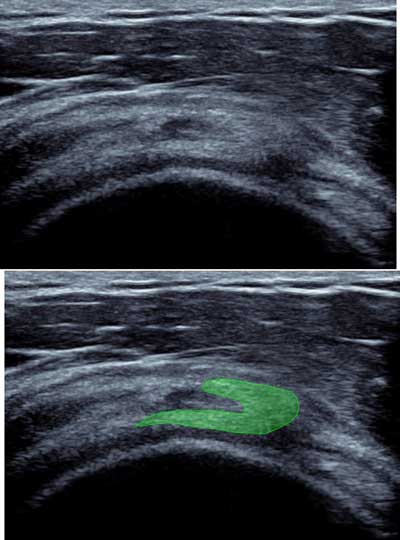

At the myotendinous junction of the supra spinatus (2cm proximal to the insertion), an anterior tendinous complex and a posterior aponeurotic portion. This was analyzed in a conventional position, hand on the buttock with shoulder on retro drive through inside-out sagittal cross sections with a “comma” appearance. This may be the root of symptomatic myotendinous crack, responsible for posterior shoulder pain (Figure 11) [9].

Figure 11

Sagittal view of the rotatorcuff with “coma” appearance of the myotendinous junction of the supra spinatus.